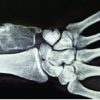

On radiological evaluation X-ray (Fig. 1 and 2) and Computed tomography (CT) Cervical spine (Fig. 3 and 4) there were 2 K-wires of unequal sizes and stainless-steel wire in lateral end clavicle across acromioclavicular joint. Another K-wire was lying at the level of C7 vertebral body lying posterior to vertebral body in the canal. A part of K-wire was lying in the spinal canal across the foramina(C7-T1) in the transverse trajectory toward transverse process. Possibly the wire from the lateral end clavicle was broken and migrated toward cervical spine in transverse trajectory. Measurements were made to localize the tip of the K-wire lying anterior to the transverse process; the lateral end of the wire was lying at 1.5–2 cm from skin surface.